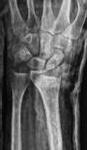

Schatzker III, Osteosinteză cu șuruburi percutană

Schatzker VI, Reducere sângerândă și osteosinteză cu 2 plăci

fracturilor cu separare sau înfundare a platourilor tibiale, precum și a leziunilor de părți moi asociate ligamentare sau de menisc.

Se practică radiografii standard, examinare CT sau RMN.

Radiografiile se fac în cel puțin 3 incidențe: antero-posterioară, laterală și notch intercondilar.

Incidența antero-posterioară poate decela: o bandă osteoscerotică intensificată, specifică fracturii cu înfundare, separarea unui fragment osos, incongruență articulară femuro-tibială. O înfundare mai mare de 6 mm sau/și o incongruență articulară cu lărgirea acesteia mai mult de 5 mm sunt sugestive pentru leziuni de menisc lateral, ligament colateral lateral sau ligament încrucișat posterior(5). O înfundare sau lărgire articulară mai mare de 8 mm este deseori asociată cu o leziune de menisc medial(6).

Incidența laterală decelează traiecte de fractură postero-mediale.

În baza examenului radiologic au fost propuse mai multe clasificări, dar cea mai folosită este cea a lui Schatzker:

Schatzker I: fracturi cu separare hemiplatou extern

Schatzker II: fracturi cu separare și înfundare hemiplatou extern

Schatzker III: fracturi cu înfundare hemiplatou extern

Schatzker IV: fracturi hemiplatou intern

Schatzker V: fracturi hemiplatou extern și intern

Schatzker VI: fracturi cu extensie metafizo-diafizară

Totuși, 10% din fracturile de platou tibial nu pot fi încadrate în clasificarea Schatzker.

CT-ul cu reconstrucție tridimensională sau RMN genunchi relevă mult mai

bine complexitatea fracturii și dau posibilitatea unui planning preoperator superior estimării radiologice clasice(7). CT-ul este mai rapid și mai ușor de făcut, dar RMN decelează mai bine leziunile de menisc sau ligamentare.

În fracturile Schatzker I, fără leziuni de menisc extern asociate este indicată reducerea și osteosinteza percutană cu șuruburi. Dacă leziunea de menisc este evidențiată pe RMN, se poate opta pentru reducere și osteosinteză percutană cu șuruburi asociată cu artroscopie(12), având rol de control al reducerii și curativ pentru leziunea de menisc, sau reducere deschisă și fixare internă cu placă și șuruburi.

La pacienții tineri cu fracturi Schatzker tip II și III se poate opta pentru reducere și osteosinteză percutană cu șuruburi asociată cu artroscopie. O altă variantă este cu grefă osoasă și reducere deschisă cu fixare internă cu placă și șuruburi. Controlul reducerii intraoperator se realizează artroscopic sau cu C arm.